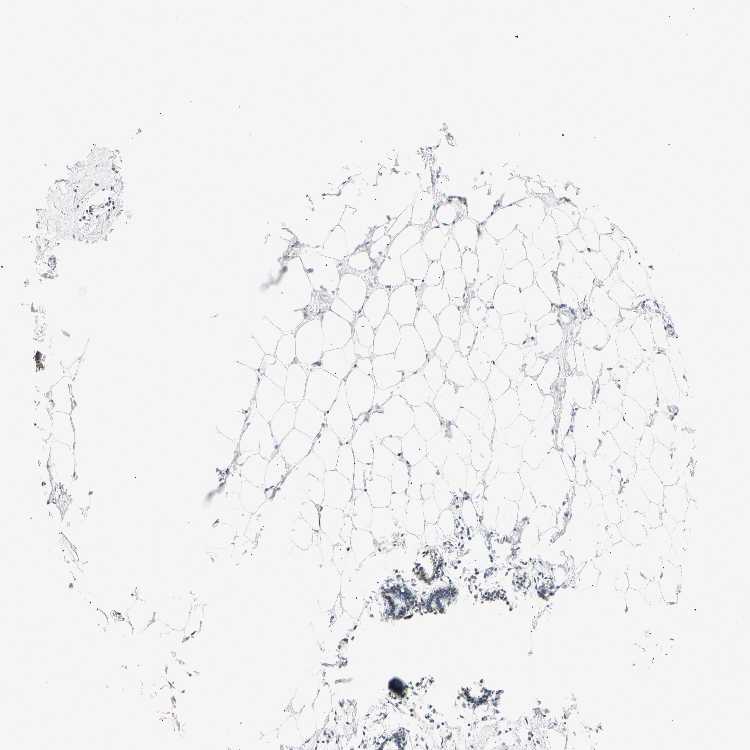

BREAST - Antibody stainingi

Antibody staining in the annotated cell types in the current human tissue is reported as not detected, low, medium, or high, based on conventional immunohistochemistry profiling in selected tissues. This score is based on the combination of the staining intensity and fraction of stained cells.

Each image is clickable and will lead to virtual microscopy that enables deeper exploration of all samples and also displays staining intensity scores, fraction scores and subcellular localization as well as patient and tissue information for each sample.

Antibody HPA008751Antibody CAB005227

Adipocytes Not detectedLow

Glandular cells Low-

Myoepithelial cells Not detected-